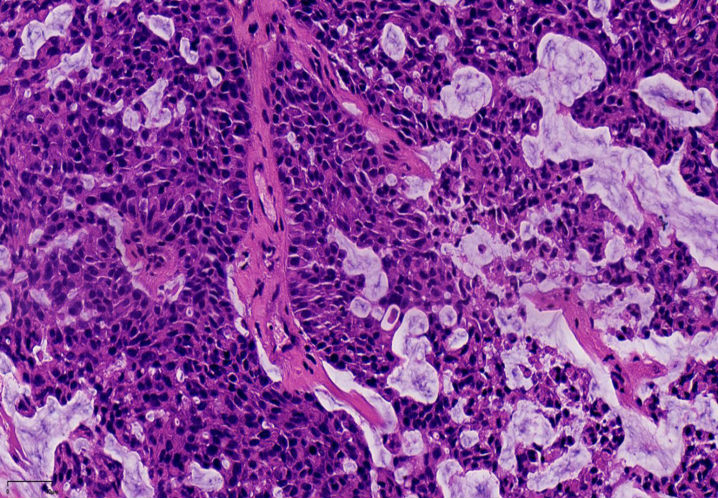

纤细的血管轴心周围细胞呈栅栏状排列

SPF细胞形态

特征性细胞:形态多样,卵圆形,梭形,多边形,印戒样或浆细胞样胞浆嗜酸性颗粒状,单形性,核低至中级别,染色细腻,可见小核仁核分裂少见(<5/10HPF)肿瘤细胞可有细胞内、外粘液形态单一,呈圆/卵圆形,胞浆淡染、嗜酸性颗粒状嗜酸性颗粒状

胞浆嗜酸性颗粒状胞浆,浆细胞样外观

流水状排列

细胞内黏液,印戒样细胞

细胞内外粘液,可以在细胞与纤维轴心之间,也可在细胞与导管壁之间细胞外黏液

1、浸润性实性乳头状癌:保留实性乳头状结构,体积大的团巢,轮廓不规则,间质促纤维反应,肌上皮缺失,原位SPC背景

浸润性SPC